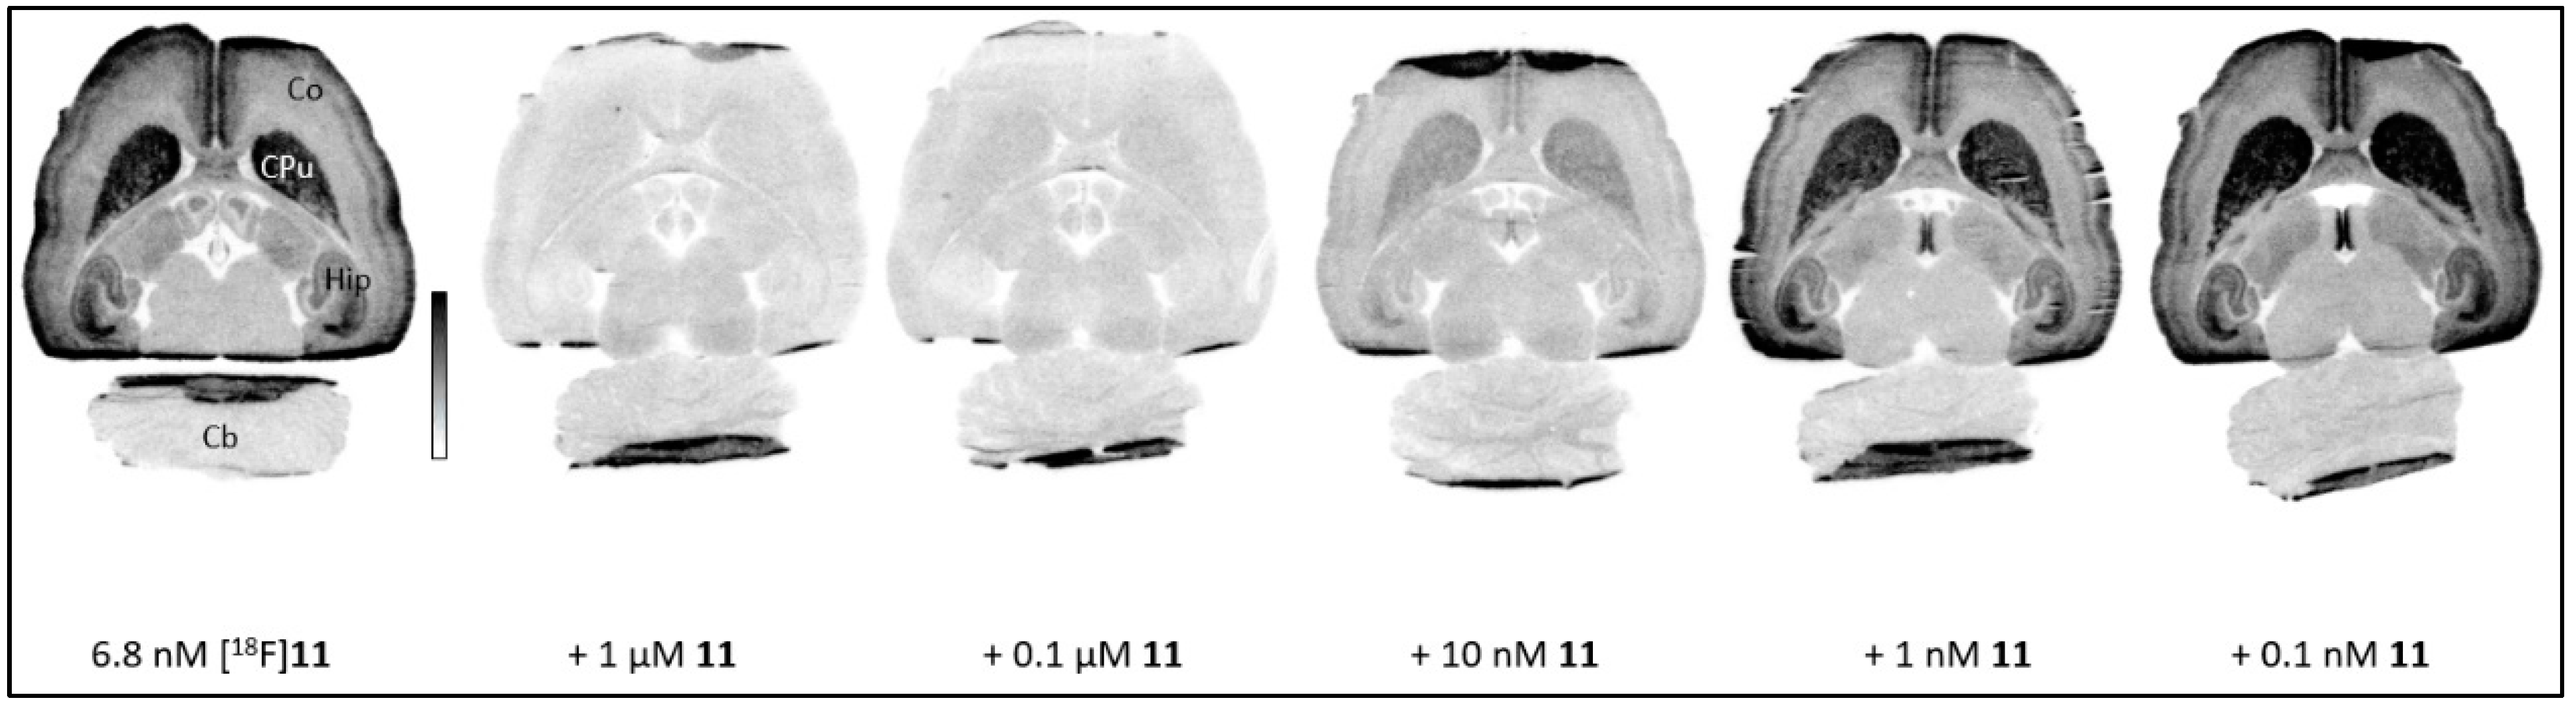

2.3.1. In Vitro Autoradiography with Rat Brain Cryosections

3.3.1. In Vitro Autoradiography